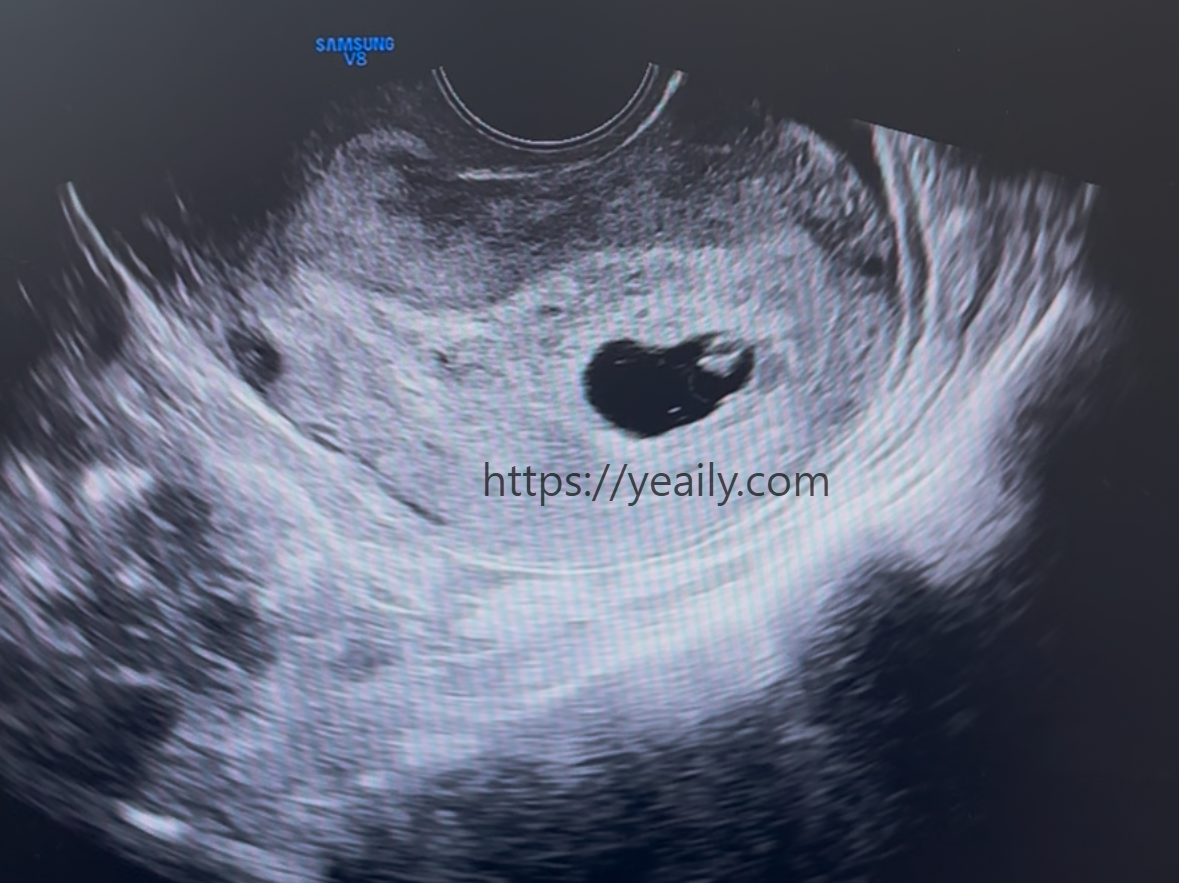

하지만 3주 뒤 다시 찾은 병원에서 저는 믿고 싶지 않은 결과를 마주해야 했습니다. NICU에서 수많은 아기들의 심장 박동을 들어왔던 간호사로서, 초음파 화면에 비친 아기의 느린 박동과 바람 빠지는 듯한 소리를 듣는 순간 직감적으로 알 수 있었죠. 계류유산이었습니다. 의료인으로서 초기 유산이 산모의 잘못이 아니라는 걸 머리로는 알지만, 마음은 '내가 무엇을 잘못했을까'라는 자책으로 무너져 내렸습니다.

의사 선생님께서는 자연 배출이 어려울 것 같아 자궁 내 잔류물을 제거하는 '소파술'을 권유하셨습니다. 수술을 위해서는 전날 자정부터 금식이 필수였고, 떨리는 마음으로 다시 병원을 찾았습니다. 수술 전 다시 한번 초음파로 상태를 확인한 뒤 본격적인 준비가 시작되었어요.